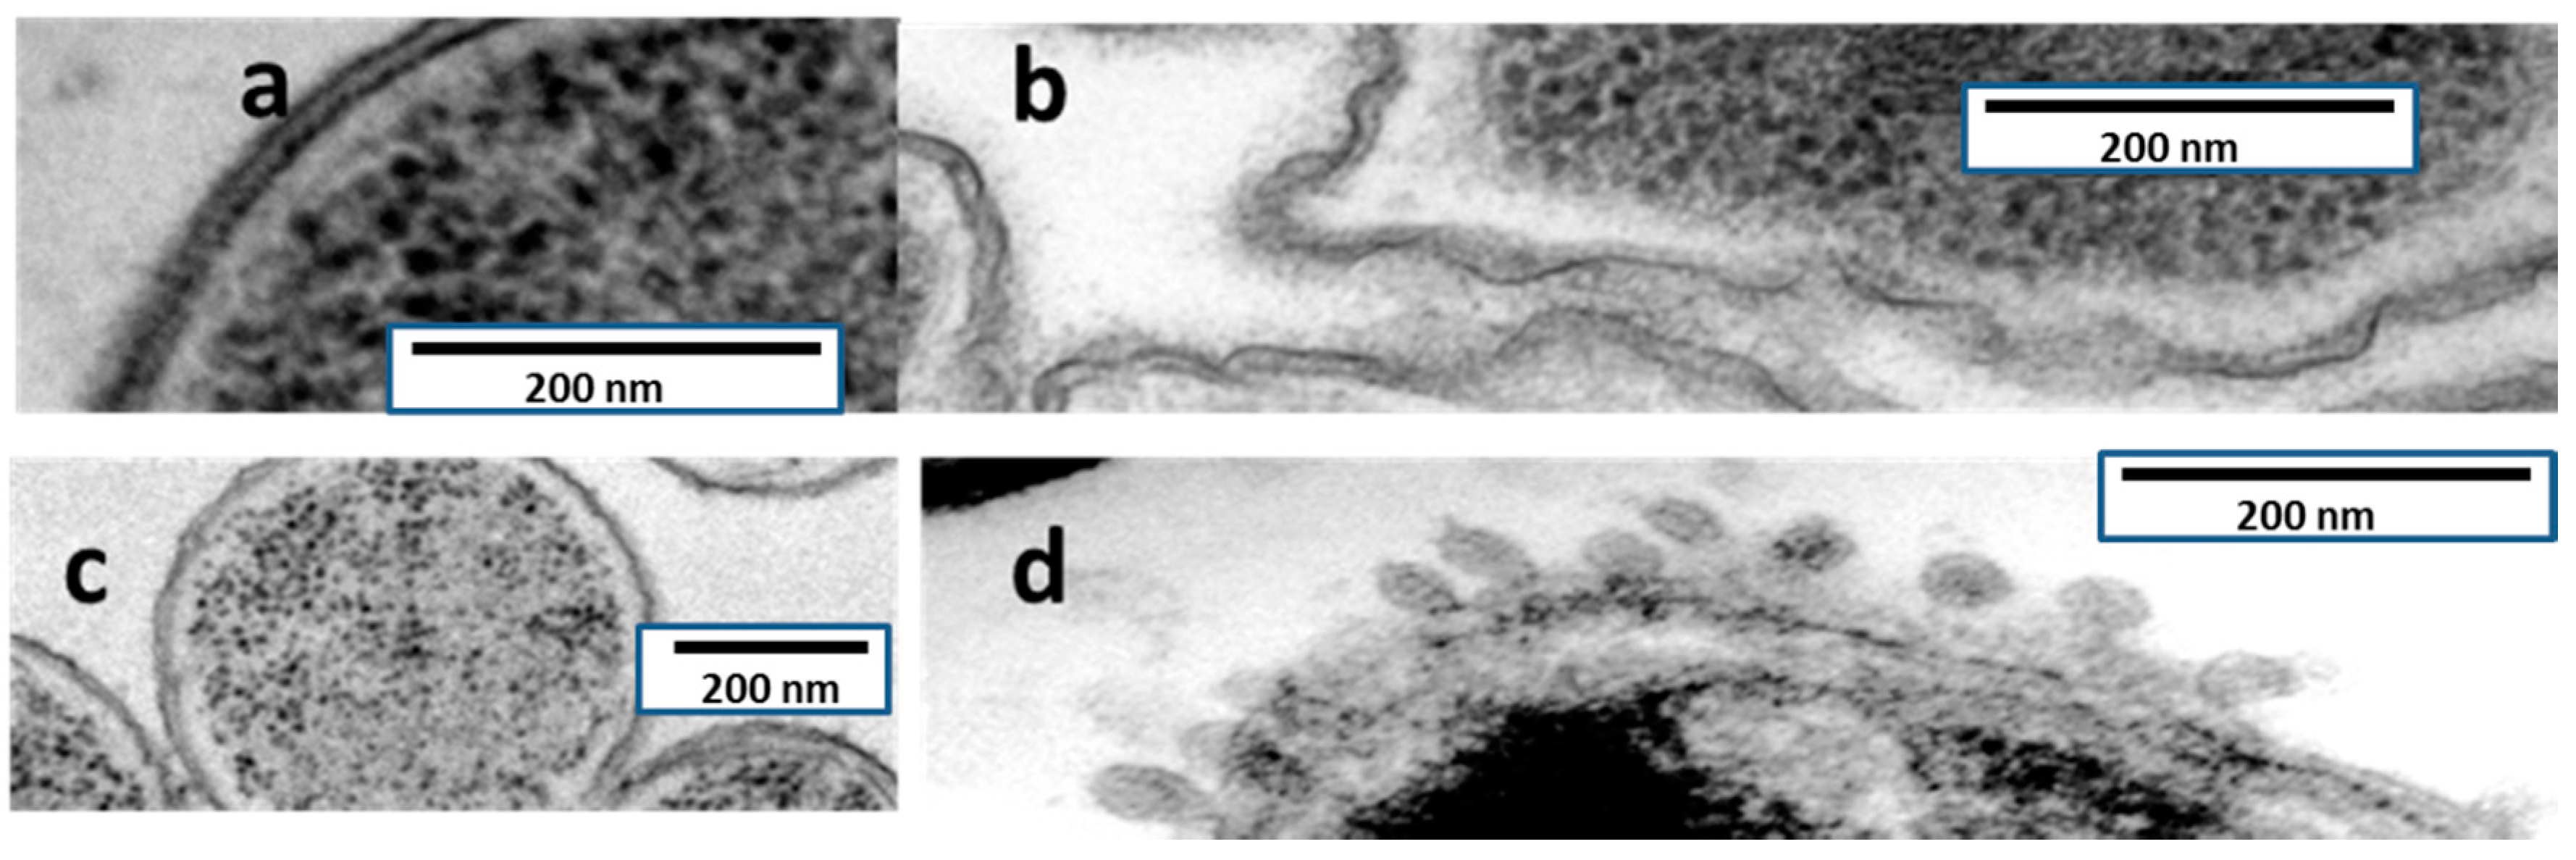

TEM observations of ultrathin sections of both P. aeruginosa and Serratia marcescens are shown in Figure 4. The effect on the bacterial envelopes is in S. marcescens is at least apparently identical to the one produced by colistin (formation of blebs), whereas in P. aeruginosa, injuries had a different aspect, lacking blebs and appearing as a rough surface.

TEM has allowed significant advances in the understanding of bacterial structure and eventually physiology [22], including antibiotic tolerance and biofilm formation. The mechanism of action of AMP38 in P. aeruginosa and S. marcescens was confirmed by examining untreated and treated bacteria with transmission electron microscopy. Untreated P. aeruginosa cells were examined by TEM. Electron micrographs of AMP38-treated P. aeruginosa (Figure 4) show a disorganized outer and inner membrane, as compared to the smoothness of untreated membranes. As a control, S. marcescens was used. This bacterium is intrinsically resistant to colistin, because although colistin disorganizes its outer membrane, it is not capable of altering the inner membrane [23], and the bacterium remains viable. Typically, the effect of colistin on S. marcescens cells is visualized as the production of blebs. We performed an ultrastructural analysis via TEM in order to explore whether colistin and AMP38 share mechanisms of action.

When S. marcescens was exposed to colistin, blebs appeared on the outer layer, but no changes were visualized in the cytoplasmic membrane (Figure 4). Figure 4 shows S. marcescens exposed to the AMP38, where the same blebs were observed in the outer membrane. Although further research has to be done, the microscopically visualized effects of AMP38 and colistin on Gram-negative bacteria seem to be similar, if not identical.

4.6. Transmission Electron Microscopy

Figure 4. TEM electromicrographs of P. aeruginosa PA116136 (a) untreated and (b) AMP38-treated; and Serratia marcescens NIMA strain (c) untreated and (d) AMP38-treated.